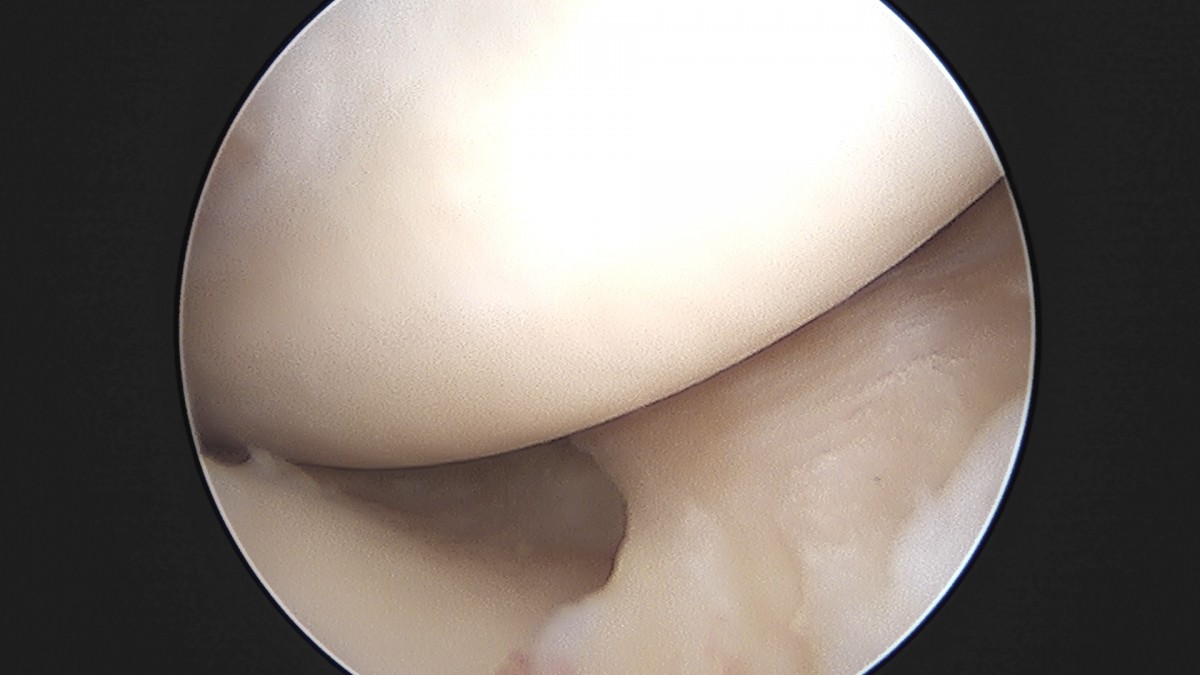

이재상원장님 무릎 반월상 연골판 절제술 고기O 환자

dae765e4d9ac96aee867c9d6292d8784_1758005092_9008.jpg